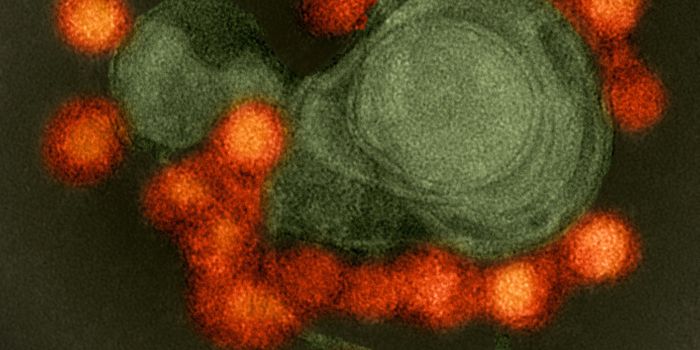

MAR 28, 2024Clinical & Molecular DXBorna disease virus (BoDV-1) has long caused fatal encephalitis, Borna virus disease in horses and sheep in Central Euro ...